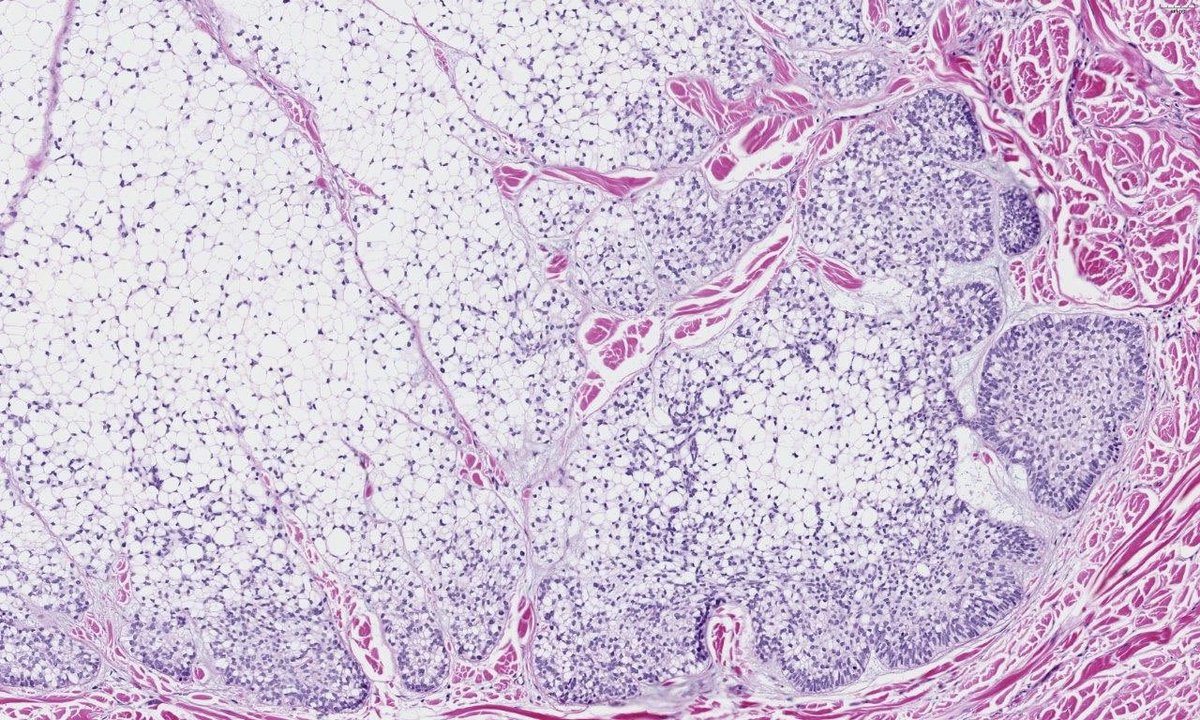

IgG4:IgG ratio >50% Plasma cell rich inflammation and storiform fibrosis and focal obliterative phlebitis, consistent with IgG4 related disease. I added IgG4 to a recent blood sample which was >12 g/L (N range =0.01–1.3 g/L) also strongly supportive of IgG4 disease.

Biopsy of hard painless submandibular gland from a 60ish yr old man. What are the immunostains and what’s the likely diagnosis?#ENTpath #PathTwitter @HeadandNeckPath